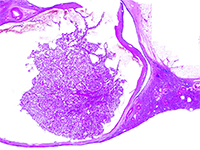

SurgeryW 2012 roku The International Society of Urological Pathology (ISUP) zaproponowało wdrożenie do klasyfikacji 5 nowych podtypów raka nerki, w tym raka nerki związanego z nabytą torbielowatością nerek (ang. acquired cystic disease - associated renal cell carcinoma - ACD-RCC). W 2016 roku ACD-RCC został uznany za niezależną jednostkę w Klasyfikacji Nowotworów Układu Moczowego WHO 2016. [1]. Poniższa praca prezentuje typowe cechy ACD-RCC w oparciu o dwa przypadki.